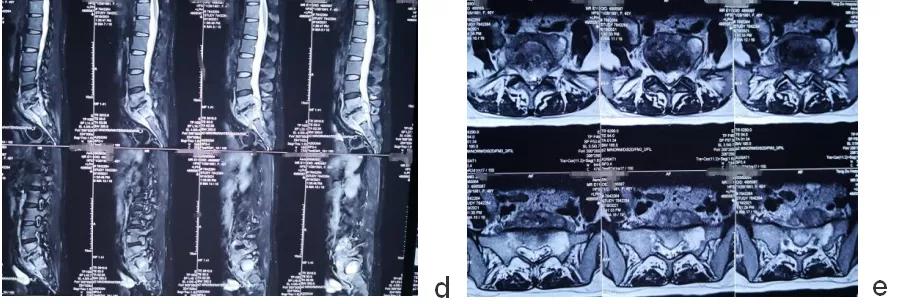

术后影像学检查

a.术后髂翼位置示双侧S2AI钉位置良好。

b.术后正侧位片示腰4/5/骶1螺钉位置良好。